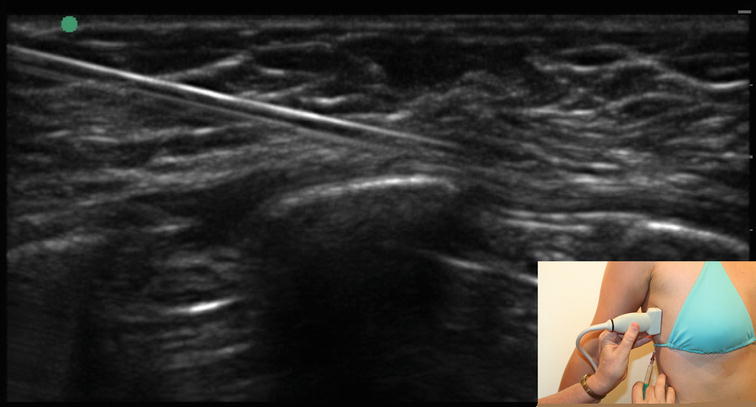

Long Thoracic Nerve Entrapment | SpringerLink